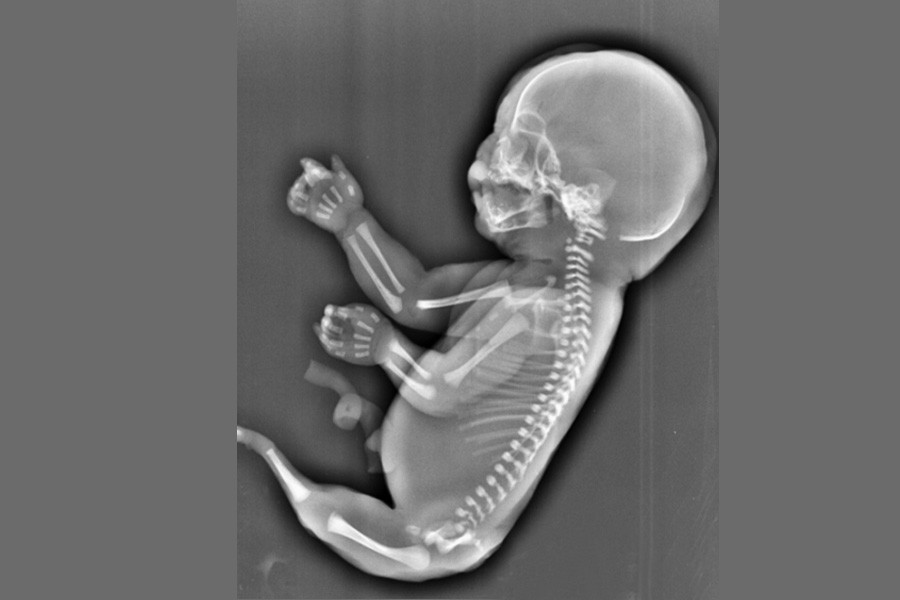

根據中國大陸媒體《三峽晚報》報導,A女到湖北省宜昌市婦幼保健院做超音波檢查,卻發現,胎兒下肢無雙腿,只有一條類似美人魚的尾巴。超聲科副主任甘茲平說,孕婦的子宮腔內沒見羊水暗區,借助胎兒骨骼影像順序連續掃查,發現胎兒頭顱、胸腔、雙上肢,也可以看到一個跳動的心臟;但下肢只找到一條股骨,未見雙腿、膀胱,只有一側發育不良的腎臟。

「從事超聲診斷30多年還是第一次真正見到這種畸形,這也是宜昌首例產前超聲確診的人體魚序列徵。」該院超聲科主任白靈子介紹,非常少見,文獻記載發病率約為1/24000至1/67000,形成可能與血管竊血現像有關。白主任說,該病無法預防,只能早發現早處理。

「美人魚綜合症」是以肛門閉鎖、泌尿生殖系統異常、下肢發育不全為特徵的綜合症,這種病症極其罕見,大概每10萬人中有1.67人可能罹患此症。武漢市第五醫院婦產科黃玲主任表示,人魚寶寶在形體畸形外,還伴有內臟器官的發育不全或完全缺失,屬於多器官致死性畸形,出生後很難生存;而在該院發現的這一例不僅缺少多個重要器官、心臟畸形,並且只有單腿,屬於該類疾病中最為嚴重的一型。